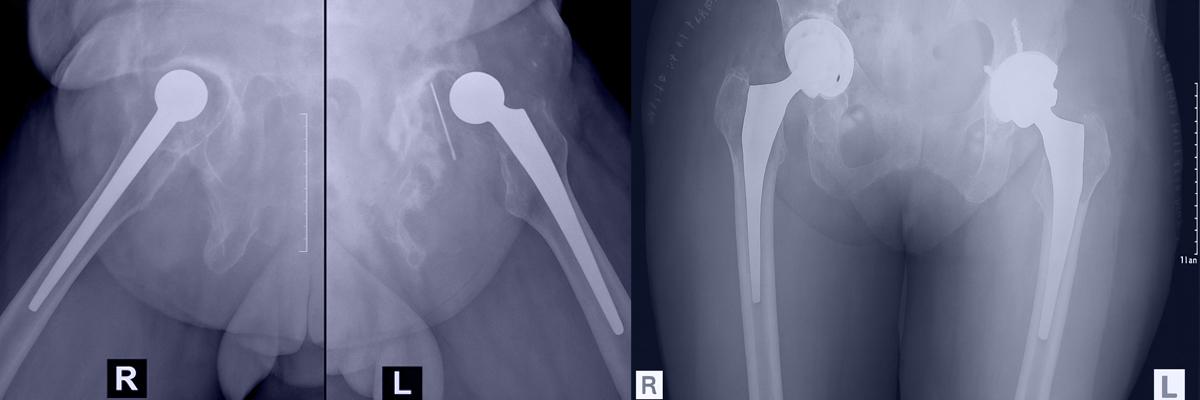

Revision Hip Replacement

Critical Insights into Second-Time Hip Replacement Surgery

1. Removing and Replacing the Old Hip Implant

Revision Hip Replacement involves removing a previously implanted artificial hip joint and replacing it with a new, customised implant to restore joint function and reduce pain or instability.

2. Common Reasons for Revision Hip Surgery

Typical indications for revision include aseptic loosening, deep infection, hip joint instability, recurrent dislocation, implant fracture, or fractures around the prosthesis.

3. Bone Loss and Muscle Damage Are Considerations

During revision, some bone loss may occur in the acetabular region and proximal femur. In many cases, the abductor muscle mechanism is also compromised. Implant selection—including cup design, liner, stem length, head size, and bearing surface—is tailored based on these structural changes.

4. Two-Stage Surgery in Infected Hip Cases

In infected hip replacements, a two-stage revision is performed. The first stage includes removing the infected prosthesis, cleaning the area, and inserting an antibiotic-loaded cement spacer or temporary prosthesis. After 6–8 weeks, a second surgery is performed to insert the new definitive implant.